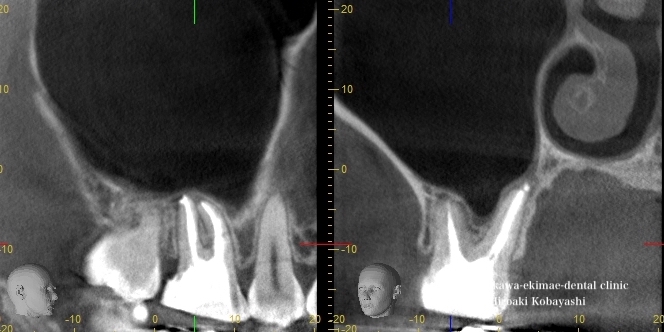

精密根管治療による上顎洞炎の治療

他院にて保険の根の処置を受けていて、中々治らず、上顎洞炎と診断され耳鼻科に受診を勧められ、しまいには抜歯を勧められ、当院にて歯を残すことができないかとご相談を受けました。

保険での限られた時間では中々、バイ菌を取り切ることは困難です。十分に時間を確保しラバーダム防湿を行い顕微鏡にて前医の取り残している感染源を除去していきます。

2回ほどの根管治療にて、上顎洞炎の病態である粘膜の肥厚も収まり、問題なく治癒しました。